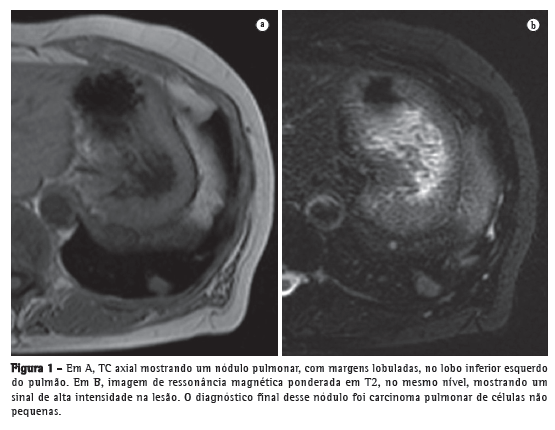

Avanços técnicos substanciais em angio-RM pulmonar foram introduzidos nos últimos anos (Figuras 5 e 6). Novas melhorias estão em andamento; dentre elas, o uso de imagens paralelas, compartilhamento de visão, angiografia do tipo time-resolved echo-shared(17-19) e perfusão pulmonar. Essas técnicas encurtaram o tempo de aquisição da angio-RM, tornaram-na menos suscetível a artefatos de movimento e melhoraram a resolução espacial. Um estudo mostrou que um protocolo combinado de RM (progressão de RM em tempo real para RM de perfusão, e desta para angio-RM) é confiável e sensível, produzindo resultados semelhantes aos obtidos com TC com multidetectores de 16 fileiras.(18)

Em 2003, Stein et al.(20) conduziram uma meta-análise do uso de RM com gadolínio para a visualização de embolia pulmonar aguda. Os autores utilizaram a angiografia pulmonar convencional como padrão de referência. Constataram que a sensibilidade relatada para o procedimento variava consideravelmente (77-100%) e que a especificidade relatada era uniformemente elevada (95-98%).(20) No mais recente dos estudos avaliados naquela meta-análise, Oudkerk et al.(21) mostraram que a sensibilidade da RM com contraste para embolia pulmonar foi de 100% nas artérias centrais e lobares, 84% nas artérias segmentares e apenas 40% nos ramos subsegmentares.

Demonstrou-se recentemente que em casos de suspeita de embolia pulmonar aguda, a RM com um protocolo de última geração com três componentes (sequência true fast imaging with steady-state precession; perfusão e angio-RM com aquisição paralela) é extremamente acurada.(18) A sensibilidade e especificidade relatadas por paciente são de 85% e 98%, respectivamente, para a sequência true fast imaging; 100% e 91% para a sequência de perfusão e 77% e 100% para a angio-RM. A sensibilidade e especificidade relatadas para o protocolo combinado são de 100% e 93%, respectivamente. Embora a RM e a angio-RM sejam específicas, têm baixa sensibilidade, particularmente para embolia pulmonar subsegmentar. No geral, o protocolo combinado de RM revelou-se mais confiável e sensível que a TC com multidetectores de 16 fileiras.(18) Relatou-se que a duração média do exame de RM é de aproximadamente 10 min.(18)